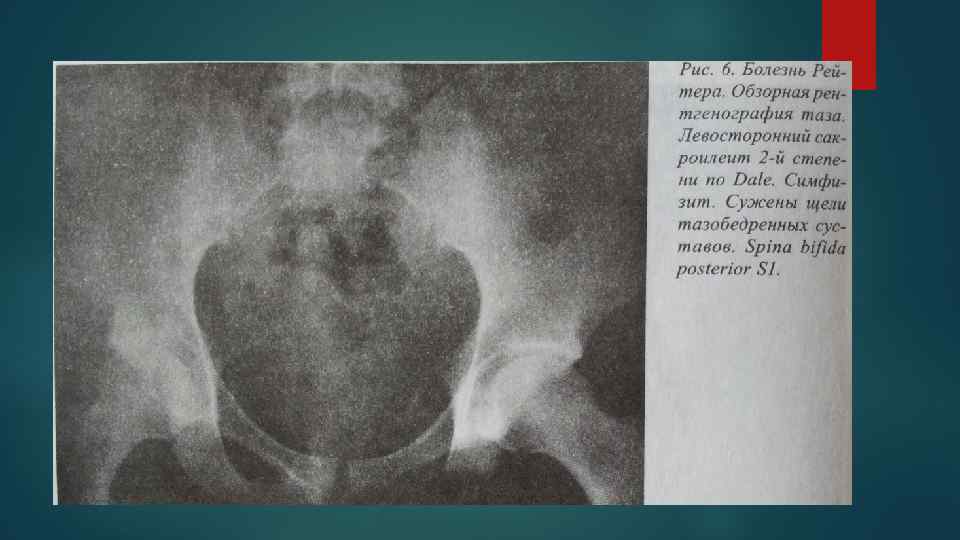

Рентгенологические изменения поражения суставов при болезни Рейтера Рентгенологические изменения поражения суставов при болезни Рейтера

Типичным для болезни Рейтера является несимметричная распространенность изменений с преобладающим вовлечением в патологический процесс Типичным для болезни Рейтера является несимметричная распространенность изменений с преобладающим вовлечением в патологический процесс костей и суставов нижних конечностей. Наиболее характерными местами изменений являются мелкие суставы дистальных отделов стоп, пяточной кости, коленные и голеностопные суставы. Реже обнаруживаются в осевом скелете, крестцовоподвздошных суставах и симфизе.

Утолщение мягких тканей связывается с внтурисуставными изменениями, периартикулярным отеком мягких тканей и воспалительными Утолщение мягких тканей связывается с внтурисуставными изменениями, периартикулярным отеком мягких тканей и воспалительными изменениями в слизистых сумках и сухожилиях. Околосуставной остеопороз Сужение суставных щелей в суставах дистальных отделов стоп. Эрозии первоначально появляются на краях суставных поверхностей, позже процесс может прогрессировать и вовлекать субхондральный отдел кости в центральной части сустава Периоститы линейные и бахромчатые

Стадии сакроилеита ( по Dale, 1979) Стадия Рентгенологические изменения 0 (норма) Нормальная ширина суставных Стадии сакроилеита ( по Dale, 1979) Стадия Рентгенологические изменения 0 (норма) Нормальная ширина суставных щелей. Суставные поверхности четкие, ровные. 1 (подозрительные изменения) На отдельных участках крестцово-подвздошных сочленений отмечается нечеткость и неровность суставных поверхностей; в центральном отделе сустава можно отметить небольшой субхондральный остеосклероз. 2 (ранние явные изменения) Начальный сакроилеит А – односторонние изменения Б – двухсторонние изменения Умеренно выраженный субхондральный остеосклероз с обеих сторон суставной щели; участки псевдорасширения суставной щели, чередующиеся с участками сужения; ограниченные участки с эрозиями суставных поверхностей; нечеткость суставных поверхностей на всем протяжении. 3 (тяжелые деструктивные изменения) Активный сакроилеит А Б Все симптомы сакроилеита 2 -й стадии резко усилены. Выраженный субхондральный остеосклероз. Множественные эрозии и на всем протяжении нечеткость контуров суставных поверхностей. Щели суставов частично не видны из-за выраженного остеослероза. Могут выявляться крупные кисты в субхондральном отделе костей. 4 (начальные регрессионные изменения) Угасающий сакроилеит А Б Уменьшается субхондральный остеосклероз. Более четкими становятся видимые участки суставных поверхностей. Появляются единичные или множественные, различных размеров, костные мостики (частичный анкилоз суставов). Суставные щели часто сужены, редко расширены. 5 (терминальные изменения) неактивный сакроилеит Полный анкилоз суставов. Полная регрессия субхондрального остеосклероза.